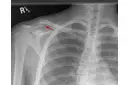

28 yıl önce trafik kazası sonucu sol kalça sağa doğru eğilerek asimetri oluşmuş sol simfizis pubis sağ simfisiz pubise dayanmış hatta sağ kalçada sağa doğru kaymış simfizis pubis penil köke baskı yapmakta, ben bu ameliyatı yapacak dr bulamadım, bana ameliyat yağabilecek dr önerebilir misiniz. Tetkik be görüntüleri göndereceğim bi mail adresi yada Watsapp numarası verirseniz hemen gönderirim. Laf olsun diye sormuyorum gerçekten pelvis eğriliğini düzeltecek dr yok sanki bu ülkede yıllardır bulamadım. Lütfen yardımcı olurmusunuz, Türkiye’deki tek vaka olabilir mişim öyle diyen dr lar da var. Yardımlarınız için şimdiden teşekkür ederim